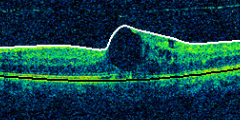

La thérapie au laser MicroPulse pour les troubles de la rétine, une thérapie qui ménage la fovéa

VA 20/50 | CRT 434 μm

3 Months Post-Op | VA 20/30 | CRT 314 μm